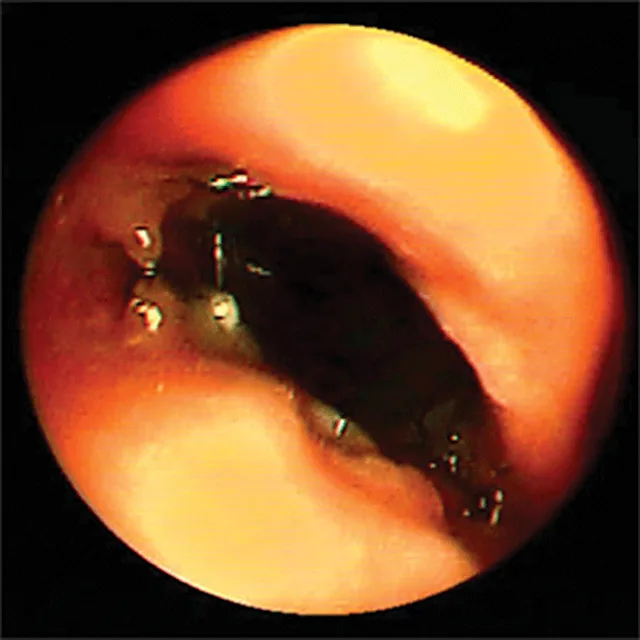

Definitive diagnosis is based on imaging (eg, survey radiography, fluoroscopy, ultrasonography, computed tomography, tracheobronchoscopy).13 Survey radiography should include dorsoventral and lateral views of the cervical region and thorax (Figure 1). Collapse of the trachea is best viewed in the cervical region during inspiration and in the intrathoracic region during exhalation.1 Radiography is critical to rule out conditions that may cause similar signs (eg, intrathoracic masses, pleural effusion) and cardiovascular abnormalities (eg, heart enlargement) that may complicate treatment. Radiography is noninvasive, cost effective, widely available, and can be performed without the risks associated with general anesthesia; however, false-positive results have been reported in 25% of dogs,14 and sensitivity ranges from 60% to 90%.2 In comparison, fluoroscopy allows direct viewing of tracheal motion during all phases of respiration, is noninvasive, and is very sensitive, although false-positive findings have also been reported with fluoroscopy.14 In one study, radiography underestimated the severity and frequency of collapse as compared with fluoroscopy.15

Lateral thoracic radiograph of a dog with tracheal collapse. The most severe area of collapse is just caudal to the thoracic inlet.